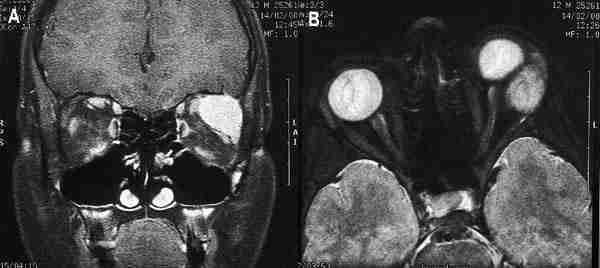

53-02.jpg (9588 bytes)

Figuras 2a, b y c. Retinoblastomas bilaterales calcificados. Imágenes axiales mediante TC (a, b) y secuencia potenciada en T2 de RM. El calcio se define mejor en el estudio de TC.

La resonancia magnética (RM) muestra menor sensibilidad en la detección de calcio que la US o la TC, sin embargo supera a estas dos técnicas en la valoración de extensión local, diseminación al SNC y en el diagnóstico diferencial con entidades que simulan al RTB (1) (figura 2c). El tumor aparece iso o levemente hiperintenso respecto al vítreo en secuencia eco de espín potenciada en T1 (SET1) en relación a hemorragia intratumoral y al depósito de sustancias paramagnéticas asociadas a calcificaciones tumorales (6) (figura 3). En secuencia eco de espín potenciada en T2 (SET2) la señal del tumor es hipointensa respecto al vítreo. El grado de extensión local se valora tras la administración de gadolinio intravenoso mediante secuencias SET1 con saturación de la grasa. Aunque el realce tumoral es variable, siempre ha de realizarse estudio con contraste ya que ayuda a identificar enfermedad retrobulbar (4).

53-03.jpg (12263 bytes)

Figura 3. Secuencia axial potenciada en T2 de retinoblastoma bilateral con hemorragia vítrea asociada en el lado izquierdo.